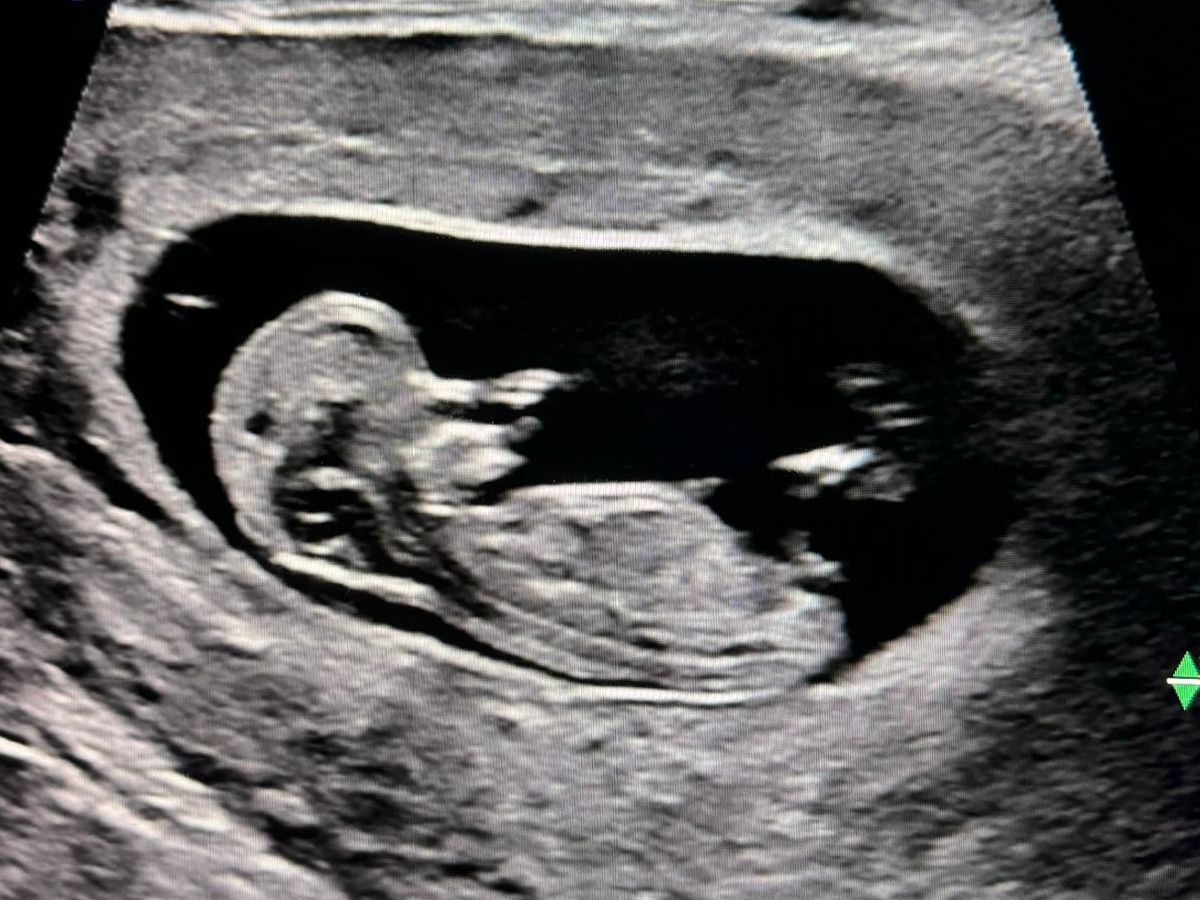

Having a family has always been our dream. After 4 years of working with fertility clinics with no success (including three failed IUI attempts and a devastating diagnosis), we decided to pursue different paths to have a family; traditional adoption and embryo adoption – the latter being the path that we chose. We had our first transfer this summer and on Emily’s 40th birthday, we received the greatest news; our adopted embryo transfer was successful. Emily was pregnant!

At our 20-week anatomy scan, we were told we were having a boy. The next day, we were told that there were significant abnormalities with the baby's heart. We were broken. After many weeks of waiting and testing with McMaster Children's Hospital and Sicks Kids Children's Hospital, it was confirmed that our son has Hypoplastic Left Heart Syndrome - a very rare and severe congenital heart disease, the cause of which is unknown. Our son will require open-heart surgery at birth, at around 6 months old and around 3 years old. Not knowing how this would play out, we decided to name him early. Our son's name is Owen James Ward. We chose this name because Owen means ‘young warrior’, and we need him to be a fighter.